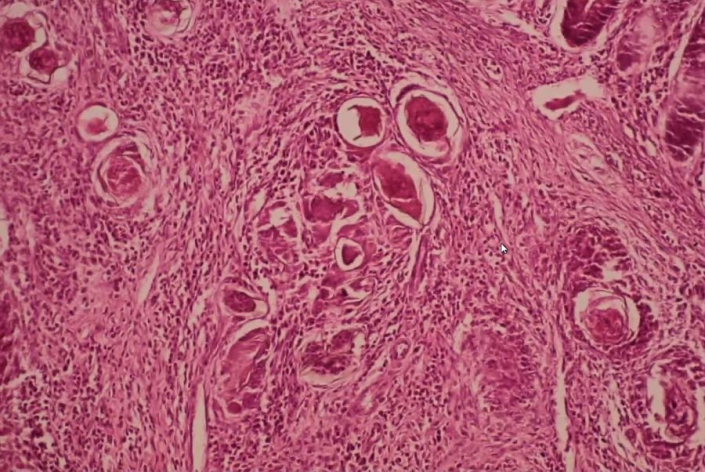

Das Mikroskop spielt eine entscheidende Rolle bei der Diagnose des Befalls mit den Trematoden-Würmern, bei der Unterscheidung der verschiedenen Erreger und dem Nachweis der Übertragungsstadien (Zerkarien) aus den Schnecken.